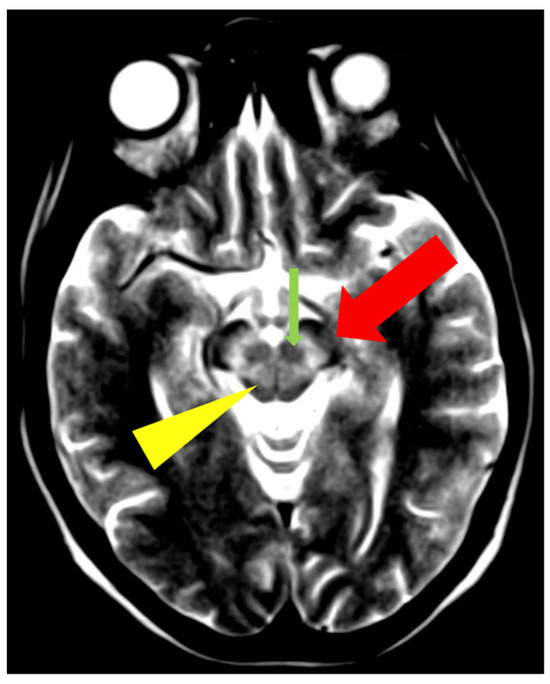

3.1. Classical Brain MRI Examination in WD Patients

5. Neuroradiological Pathognomonic Signs of WD